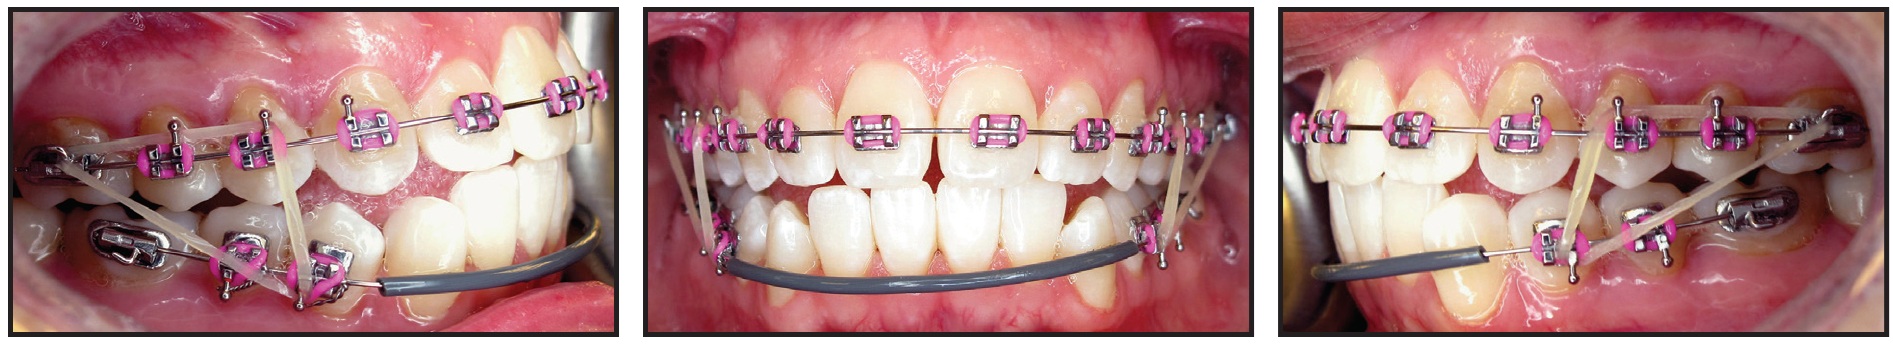

Orthodontic treatment was then initiated by bonding the maxillary arch. The archwire sequence progressed to .018" stainless steel over three months, and the lower first molars were allowed to erupt vertically into the occlusion (Fig. 5). Four weeks later, the orthotic was cut off distal to the second premolars, and elastics were prescribed from the upper to lower first molars while the patient wore the orthotic continuously.

Fig. 5 Maxillary arch bonded, with wire sequence progressing to .018" stainless steel over three months. Lower first molars allowed to erupt vertically into occlusion; note first molars in constructed bite without orthotic in place.

After two more months, the orthotic was cut off distal to the canines, and the lower first and second premolars were bonded to enable their vertical eruption (Fig. 6).

Fig. 6 Orthotic cut off distal to canines; lower first and second premolars bonded to enable vertical eruption.

Another three weeks later, a full archwire was inserted, with comfort tubing in the anterior region, and Class III vertical elastics were worn while the patient maintained orthotic wear from canine to canine (Fig. 7).

Fig. 7 Full archwire with anterior comfort tubing and Class III vertical elastics.

Eight weeks later, Class III sliding jigs were added, extending to the lower second molars, to provide direct distalization for Class III correction (Fig. 8). Elastics were worn from the upper first molars to anterior hooks on the sliding jigs.

Fig. 8 Class III sliding jigs extended to lower second molars to provide direct distalization for Class III correction; elastics attached from upper first molars to anterior hooks on sliding jigs.